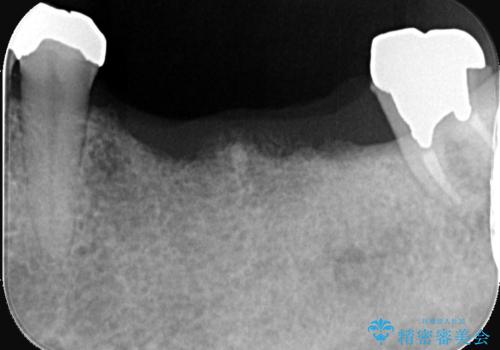

- 左下の奥歯(6番と7番)を失い、現在ご使用の部分入れ歯の不満(動く、噛めない)を主訴にご来院されました。患者様から「しっかりと噛める歯を取り戻したい」という強いご希望があり、精密な診査の結果、残りの歯への負担が少なく、最も安定した機能回復が期待できるインプラント治療を提案しました。治療計画は、左下6番と7番の欠損部に2本のインプラントを埋入し、約3ヶ月で最終的な歯まで装着することを目指しました。

今回の治療では、まず左下6番と7番の欠損部に、骨の状態を考慮しながら慎重に2本のインプラントを埋入しました。インプラント体と骨がしっかりと結合するのを待った後、最短の期間で最終的な被せ物を装着するための精密な型取りを実施。最終的に、周囲の歯と調和した審美性の高いセラミック製の歯を装着しました。